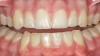

Figure 5  Preoperative photograph of tooth A.

Figure 5